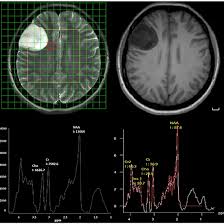

MRI 3D Multivoxel Spectroscopy is an advanced imaging technique used to analyze the brain’s metabolic and biochemical composition. This non-invasive MRI 3D spectroscopy procedure provides detailed images, offering detailed information into various brain-related issues and brain disorders/Cerebral conditions. Through Multivoxel MR spectroscopy, it can identify abnormalities that may be undetectable with traditional MRI scans, such as brain tumors, epilepsy (seizure disorders), and metabolic conditions. With its capability to perform 3D MRI spectroscopy for brain tumor analysis and MRI spectroscopy for tumor detection, this technology is crucial for early diagnosis and treatment planning. Whether you’re looking for MRI brain spectroscopy test services or concerned about 3D MR spectroscopy for brain tumor analysis, Medifyhome partners with certified diagnostic centers to offer this cutting-edge service at affordable rates. With MRI 3D spectroscopy for neurological conditions, you can trust in accurate, reliable results that aid in effective treatment decisions.

MRI 3D Multivoxel Spectroscopy is a specialized imaging procedure used to assess brain health by providing detailed, high-resolution images of the brain’s metabolic and biochemical composition. Unlike traditional MRI scans, this advanced technique focuses on the analysis of the brain’s chemical structure, which can help detect brain-related disorders, brain disorders, and tumors. This non-invasive MRI 3D spectroscopy procedure is essential for identifying minor changes in the brain’s functioning that might not be visible in standard scans.

Through MRI spectroscopy 3D imaging, doctors gain a deeper understanding of various conditions affecting the brain, such as epilepsy, brain tumors, or other neurological disorders. By capturing images of multiple brain regions simultaneously, 3D Multivoxel MR spectroscopy offers greater clarity and precision than traditional imaging, assisting healthcare professionals in making more informed diagnoses.